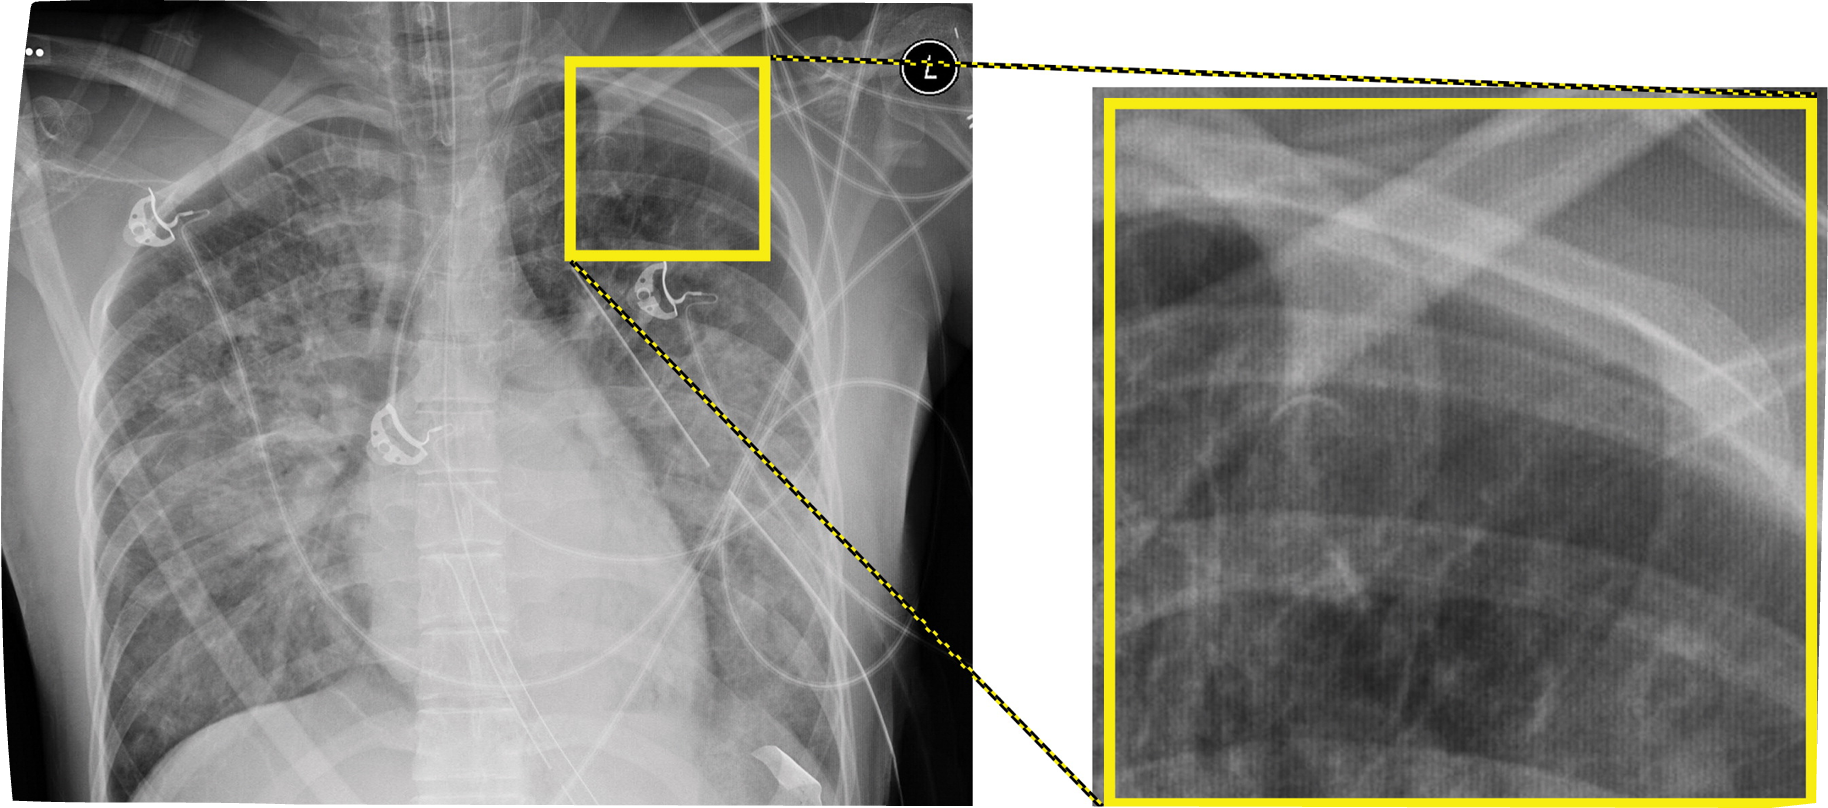

In DR systems, dead detector elements (dexels) can fail = not produce a gray square = broken

Entire rows or columns of dexels can also drop out due to electronic failure

Mild - moderate issues are compensated for

Many rows (severe), the detector plate will need to be replaced

Software can compensate for moderate cases of Dexel Drop-out, but not for severe cases like this (image), where whole sections of rows have dropped out